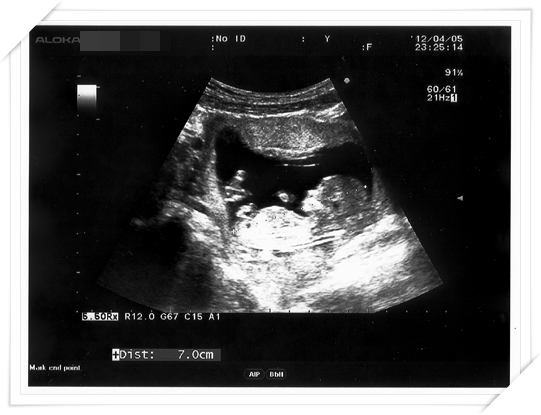

這次產檢 醫生也順便幫我做了頸部透明帶的測量

通常是跟第一期母血唐氏症篩檢一起做的

就是看看唐氏症的機率囉

然後做頸部透明帶的時候

醫生還順便照了照Baby 的鼻骨

給我們看看 baby 已經發育出來挺挺的鼻骨 (還好不像我扁鼻子!!!!)

但其實醫生是說 唐氏症寶寶比較容易沒有鼻骨 (鼻子扁扁的)

所以如果鼻骨有正常發育 是唐氏症寶寶的機率就會比較低囉

給我們另一個參考的小指標